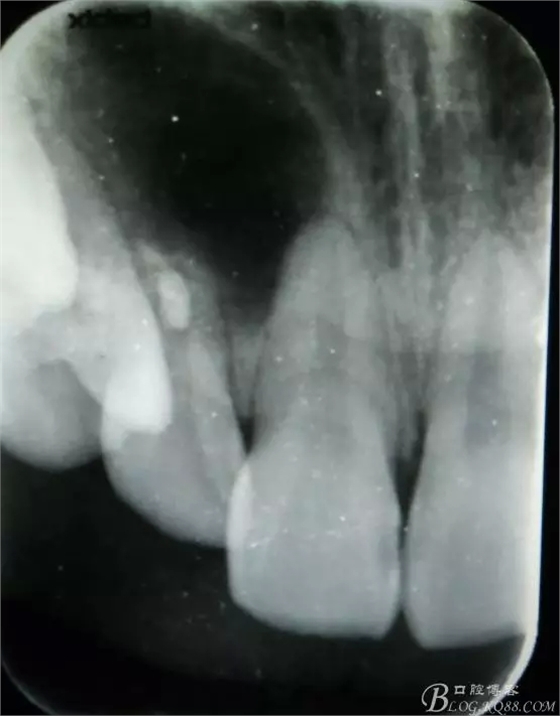

病例資料: 患者、柴xx、女、16歲。??茩z查及病歷如下圖: 患者同意我院正畸科建議,遂轉(zhuǎn)診倒外科。術(shù)前簽知情同意書。 治療過(guò)程: 圖1.術(shù)前的CBCT檢查:13阻生,疑為含牙囊腫??v剖面顯示12牙根吸收至根尖1/3。 圖2.局部麻醉下 。行唇側(cè)弧形切口,12松動(dòng)不到1°。 圖3.翻瓣、暴露骨面。 圖4.去骨、 暴露13牙冠 圖5.去骨、逐漸顯露13。 圖7.拔除13. 圖8.摘除囊壁 圖9.必須完整剝離囊壁。 圖10.摘除囊壁后形成的骨腔 圖11.超聲骨刀12根尖倒預(yù)備 圖13. 消毒棉球骨腔內(nèi)隔濕血液,紙尖干燥倒預(yù)備好的根管 圖14. 紙尖無(wú)血即可 圖15。MTA倒充填 圖16.骨腔填塞膠原蛋白海綿 圖17.拔除的13及摘除的囊壁 圖18.縫合 圖19.術(shù)后x線根尖片影像:MTA封閉根尖